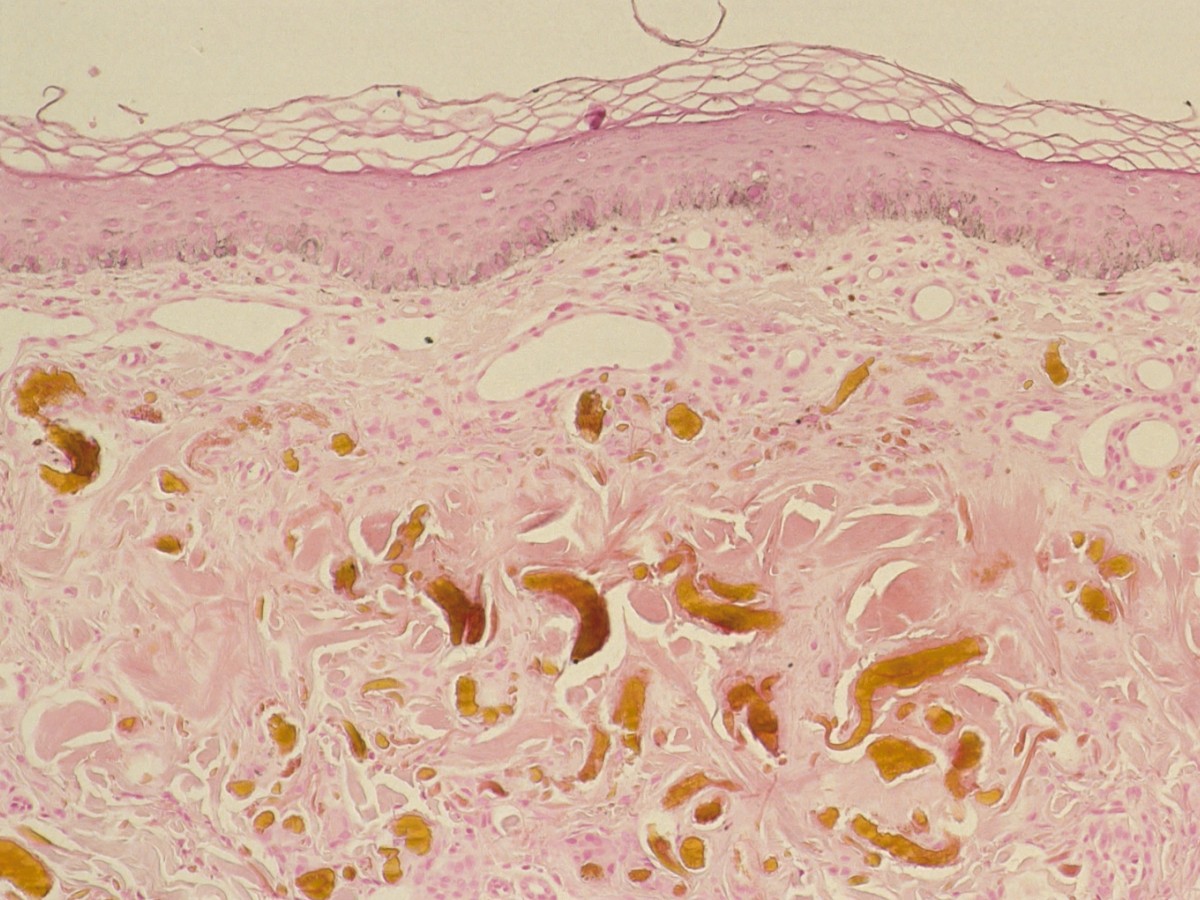

Stadia 1 en 2 vertonen doorgaans hyperkeratose met een dunne epidermis. In de dermis bevinden zich geel-bruine (okerkleurige) fibrillen die in vroege stadia eosinofiel, later basofiel en ten slotte okerachtig aankleuren. De okerkleurige fibrillen liggen verweven in elastische en collagene vezels die gezwollen en gehomogeniseerd zijn. In het bovenste deel van de dermis kan men pigmentincontinentie en melanofagen aantreffen. Stadium 3 wordt gekenmerkt door klompen ochronotisch materiaal met daartussen sarcoïd-achtige granulomen met multinucleaire reuscellen. Het ochronotisch materiaal kleurt zwart aan met Fontana Masson en blauw-zwart met methyleenblauw. De vezels kleuren echter niet aan met elastine-, PAS-, lipofuchsine- en ijzerkleuring.